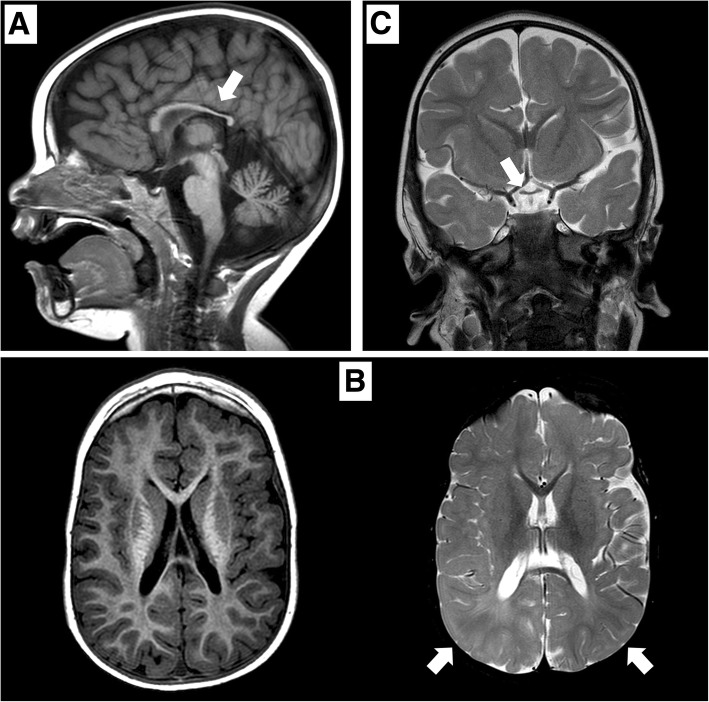

矢狀位 T1 加權(quán)圖像顯示胼胝體發(fā)育不全(白色箭頭)。 b 軸向 T1 加權(quán)(左)和軸向 T2 加權(quán)(右)圖像顯示胼胝體發(fā)育不全和雙側(cè)皮層下頂葉白質(zhì)(白色箭頭)中改變的、不明確的信號(hào)。 c 顯示視交叉發(fā)育不全的冠狀 T2 加權(quán)圖像(白色箭頭)

在 2 歲時(shí),患者無(wú)法保持目光接觸,也沒(méi)有發(fā)展語(yǔ)言技能。 直到 3 歲時(shí),他才能獨(dú)立坐下。此時(shí),頭顱 MRI 顯示雙側(cè)視神經(jīng)發(fā)育不全,并證實(shí)胼胝體發(fā)育不全(圖 (圖 1).1)。 為評(píng)估先天性心臟缺陷而進(jìn)行的超聲心動(dòng)圖顯示無(wú)阻塞的室間隔肥大。